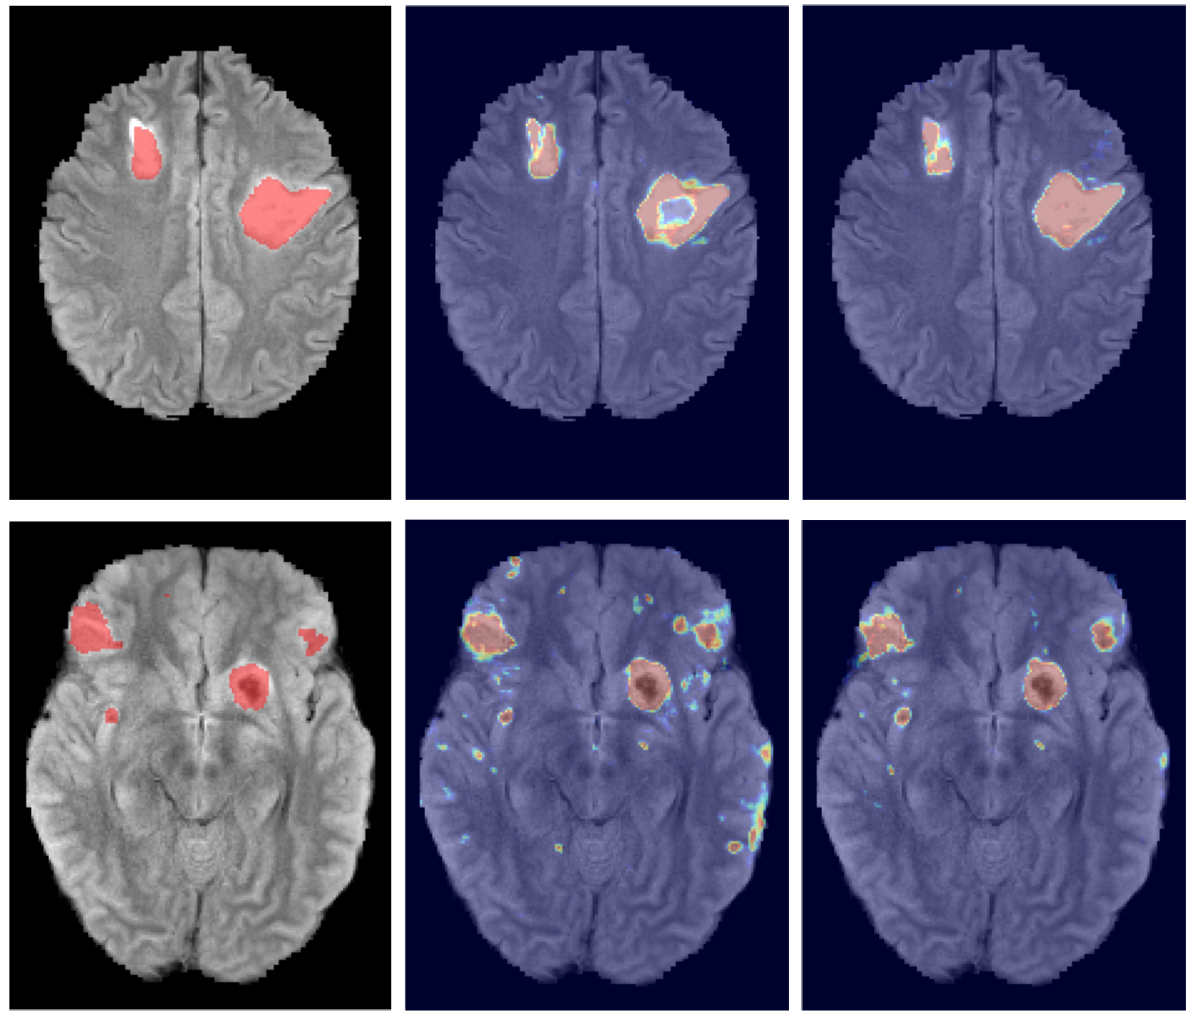

Figure 8 shows the improvement DeepMedic achieves over the single pathway model Deep+. In Fig. 9 we show two representative visual examples of this improvement when using the multi-scale CNN. Finally, we confirm that the performance increase can be accounted to the additional context and not the additional capacity of DeepMedic. To this end, we build a big single-scale model by doubling the FMs at each of the 9-layers of Deep+ and adding two hidden layers. This 11-layers deep and wide model, referred to as “BigDeep+”, has the same number of parameters as DeepMedic. The performance of the model is not improved, while showing signs of over-fitting.

The performance of our system on the training data is shown in Table 4. Significant improvement is achieved by the structural regularisation offered by the CRF, although it could be partially accounted for by overfitting the training data during the CRF’s configuration. Examples for visual inspection are shown in Fig. 13.